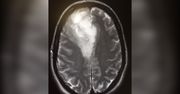

Joanna Górska, prezenterka telewizji Polsat, wygrała walkę z rakiem. Dziennikarka przyznaje, że nie byłoby to możliwe, gdyby nie jej partner. - Gdyby nie Robert, to bym umarła - mówi w rozmowie z Klaudiuszem Michalcem. Choć przeszła długą drogę i miała żal do świata, że to właśnie ją spotkała choroba, teraz otwarcie mówi, czego ją ona nauczyła i jakie ma plany na przyszłość. O nowotworze, potędze miłości, rodzinie i o tym, czy weźmie udział w „Tańcu z gwiazdami” opowiedziała reporterowi WP. Zapraszamy na drugą część wywiadu z Joanną Górską.